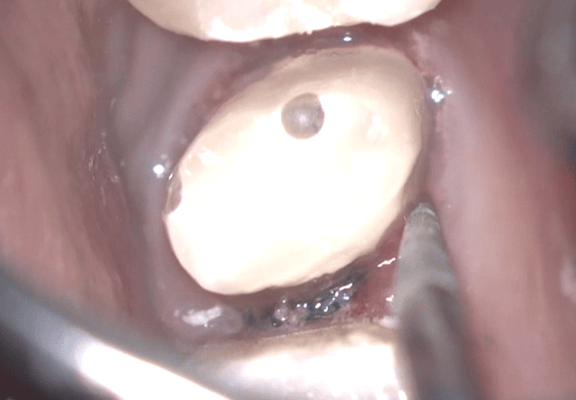

写真はすべてミラー像です。上顎左側側切歯遠心面の大きな虫歯です。エキスカで丁寧に軟化象牙質を除去していくと、歯髄腔まで本当に皮一枚になりました。血流が見えるようです。エキスカから伝わる組織の硬軟の感覚と対物-接眼レンズからの像が ”皮一枚”を達成できたと思います。皮一枚ですが、硬組織は残っていますので、ティース・プライマーを塗布し、スーパーボンド・ラジオオペークとバルクベースにて覆髄をしました。もちろん、1ケ月後の歯髄診でも陽性反応を示し、歯髄は生きています。